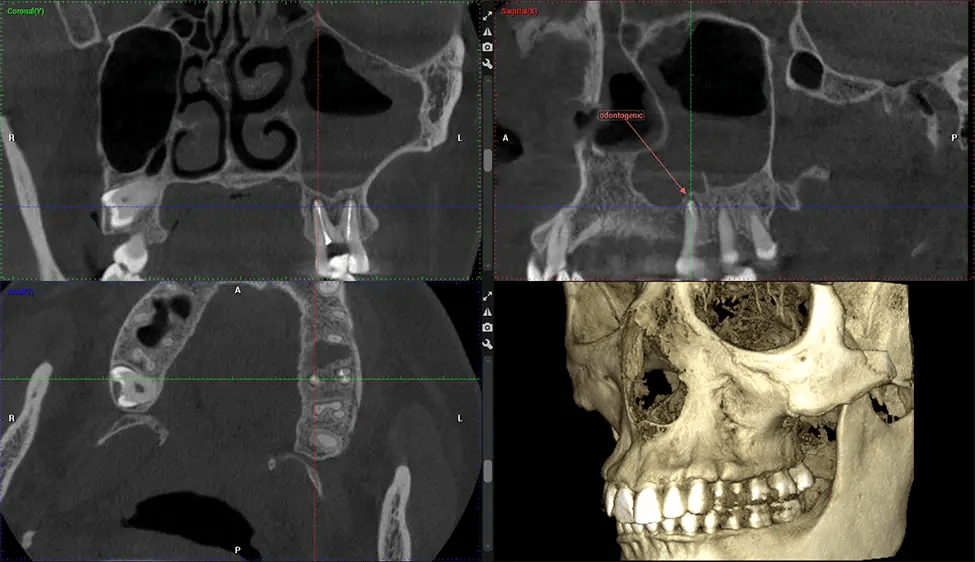

Oral and Maxillofacial Surgeon Complex oral surgeries, orthognathic (jaw) surgery, and removal of impacted teeth. Offers precise, three-dimensional visualization of the skull, jaw, and craniocervical junction to enhance diagnostic accuracy and minimize surgical risks.

Orthodontist Assessing facial asymmetry, planning orthognathic surgery, and managing cleft lip and palate and sleep apnea. Provides a comprehensive view of the craniofacial complex to better plan treatments and evaluate outcomes.

There are many benefits to using CBCT technology, especially compared to the traditional 2D X-ray format. One of the most significant advantages of CBCT scans is that they provide much more information than traditional X-rays. A scan lets your dentist see images from all angles of your jaw and mouth, including your sinuses, nasal cavity, cheekbones, and other surrounding areas. This added information helps your dentist craft a comprehensive treatment plan that addresses all aspects of your oral health.